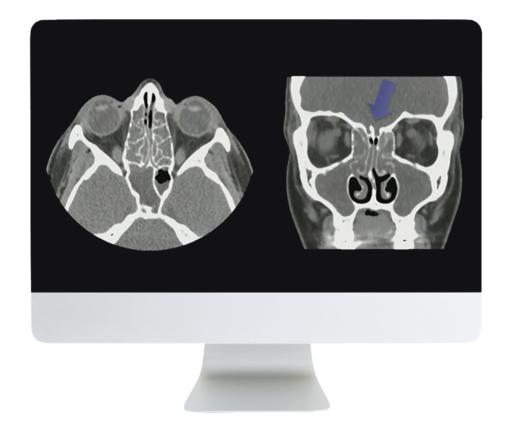

- Can’t Smell a Thing: Approach to Evaluation of Anosmia—Greg Avey